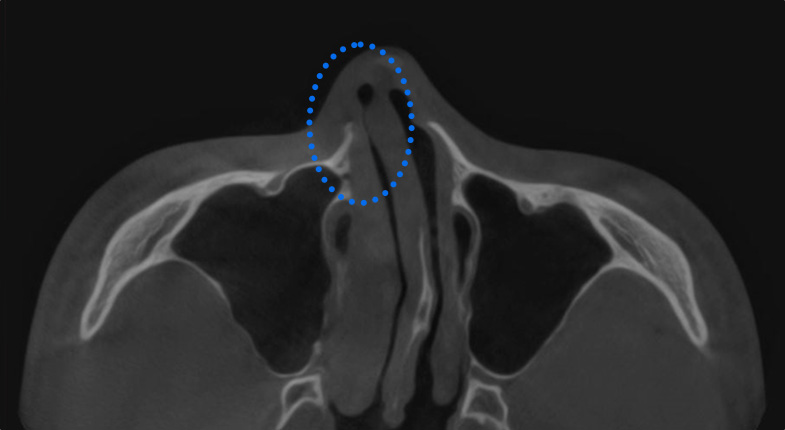

비중격 만곡증

코의 중앙에 수직으로 위치해 코의 중심을 잡아주는 비중격이 C자나 S자 형태로 휘어진 상태

휘어진 비중격 연골 일부를 제거 후 중앙에 반듯하게 재배치하여 고정합니다.